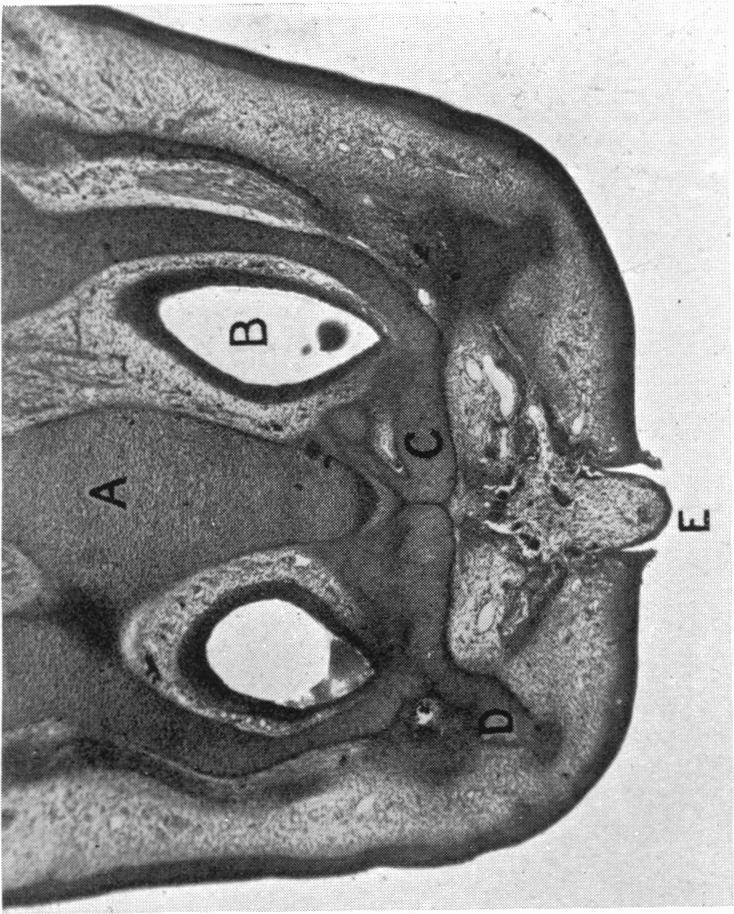

Green H L

University of Cambridge.

J Anat. 1930 Jul;64(Pt 4):512-522.1.